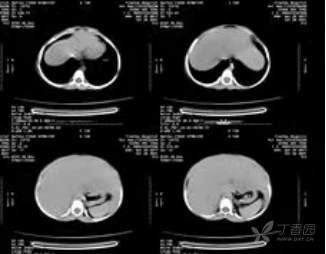

全腹CT平扫:1、肝肿大,请结合临床进一步检查;2、腹膜后淋巴结增大(如图)